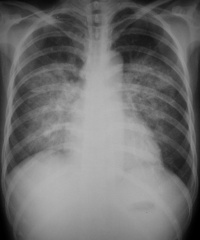

本病可严重影响呼吸功能,是临床上较常见的急性呼吸衰竭的病因。主要临床表现为极度呼吸困难,端坐呼吸,紫绀,大汗淋漓,阵发性咳嗽伴大量白色或粉红色泡沫痰,双肺布满对称性湿啰音,X线胸片可见两肺蝶形片状模糊阴影,晚期可出现休克甚至死亡。动脉血气分析早期可有低O2、低CO2分压、严重缺O2、CO2 潴留及混合性酸中毒。

肺水肿间质期的X线表现主要为肺血管纹理模糊,增多,肺门阴影不清,肺透光度降低,肺小叶间隔增宽。两下肺肋膈角区可见与胸膜垂直横向走行的KerleyB线,偶见上肺呈弧形斜向肺门较KerleyB线长的KerleyA线。肺泡水肿主要表现为腺泡状致密阴影,呈不规则相互融合的模糊阴影,弥漫分布或局限于一侧或一叶,或从肺门两侧向外扩展逐渐变淡成典型的蝴蝶状阴影。有时可伴少量胸腔积液。但肺含量增加30%以上才可出现上述表现。CT和核磁共振成像术可定量甚至区分肺充血和肺间质水肿,但费用昂贵。

- 分布和形态呈多样性,可呈中央型、弥漫型和局限型。中央型表现为两肺中内带对称分布的大片状阴影,肺门区密度较高,形如蝶翼称为蝶翼征。局限型可见于一侧或一叶,多见于右侧。除片状阴影外,还可呈一个或数个较大的圆形阴影,轮廓清楚酷似肿瘤。